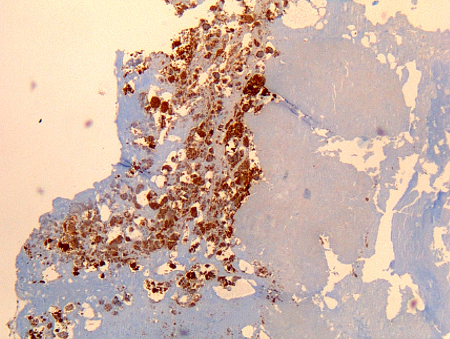

imuno-histoquímica

Exame

Considerada padrão ouro para Coxiella burnetii, mas realizada somente em laboratórios especializados.

A imuno-histoquímica tem a vantagem de conseguir identificar a infecção bacteriana em diferentes tipos de célula, mas não é tão sensível quanto a hibridização in situ fluorescente (FISH).[Figure caption and citation for the preceding image starts]: Osteíte por Coxiella burnetii: imuno-histoquímica: a coloração marrom identifica bactérias em monócitos/macrófagos.Hubert Lepidi, Institut Hospitalo-Universitaire Méditerranée Infection [Citation ends].

[Figure caption and citation for the preceding image starts]: Fibrose pulmonar por Coxiella burnetii: imuno-histoquímica; a coloração marrom identifica bactérias em monócitos/macrófagos.Hubert Lepidi, Institut Hospitalo-Universitaire Méditerranée Infection [Citation ends].

[Figure caption and citation for the preceding image starts]: Endocardite por Coxiella burnetii: imuno-histoquímica. Observe o baixo nível de inflamação. A coloração marrom identifica bactérias em monócitos/macrófagos dentro. Geralmente a vegetação está ausenteHubert Lepidi, Institut Hospitalo-Universitaire Méditerranée Infection [Citation ends].

[Figure caption and citation for the preceding image starts]: Linfadenite crônica por Coxiella burnetii: imuno-histoquímica. Observe a célula infectada isolada (monócitos/macrófagos) no linfonodo. A coloração marrom identifica bactérias em monócitos/macrófagosHubert Lepidi, Institut Hospitalo-Universitaire Méditerranée Infection [Citation ends].

[Figure caption and citation for the preceding image starts]: Hepatite crônica por Coxiella burnetii de um paciente com endocardite: imuno-histoquímica. Observe a ausência de granuloma em forma de "donut" observada na febre Q aguda. A coloração marrom identifica bactérias em monócitos/macrófagosHubert Lepidi, Institut Hospitalo-Universitaire Méditerranée Infection [Citation ends].